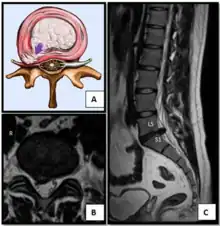

Intradural disc herniation is a rare form of disc herniation with an incidence of 0.2–2.2%. Pre-operative imaging can be helpful for diagnosis, but intra-operative findings are required for confirmation.[25]

Nucleus herniating through tear in annulus (with MRI)[8]

- Magnetic resonance imaging is the gold standard study for confirming a suspected LDH. With a diagnostic accuracy of 97%, it is the most sensitive study to visualize a herniated disc due to its significant ability in soft tissue visualization. MRI also has higher inter-observer reliability than other imaging modalities. It suggests disc herniation when it shows an increased T2-weighted signal at the posterior 10% of the disc. Degenerative disc diseases have shown a correlation with Modic type 1 changes. When evaluating for postoperative lumbar radiculopathies, the recommendation is that the MRI is performed with contrast unless otherwise contraindicated. MRI is more effective than CT in distinguishing inflammatory, malignant, or inflammatory etiologies of LDH. It is indicated relatively early in the course of evaluation (<8 weeks) when the patient presents with relative indications like significant pain, neurological motor deficits, and cauda equina syndrome. Diffusion tensor imaging is a type of MRI sequence used for detecting microstructural changes in the nerve root. It may be beneficial in understanding the changes that occur after herniated lumbar disc compresses a nerve root, and might help in differentiating the patients that need surgical intervention. In patients with a high suspicion of radiculopathy due to lumbar disc herniation, yet the MRI is equivocal or negative, nerve conduction studies are indicated.[43] T2-weighted images allow for clear visualization of protruded disc material in the spinal canal.

MRI scan of cervical disc herniation between C5 and C6 vertebrae.

MRI scan of cervical disc herniation between C6 and C7 vertebrae

MRI scan of large herniation (on the right) of the disc between L4 and L5 vertebrae

A rather severe herniation of the L4–L5 disc

Example of a herniated disc at L5–S1 in the lumbar spine